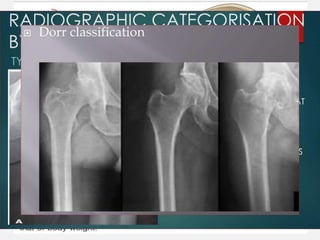

ROENTEGENOGRAPHIC EVAL U ATION

• AP view of pelvis with both hips with upper third femur with

limbs in 15degrees internal rotation.

• Spine, knee x-ray taken Note the following :

• Acetabulum : Bone stock, floor, migration, protrusio,

osteophytes and cup size.

• Femur : Medullary cavity (size & shape). Limb length

discrepancy Neck.